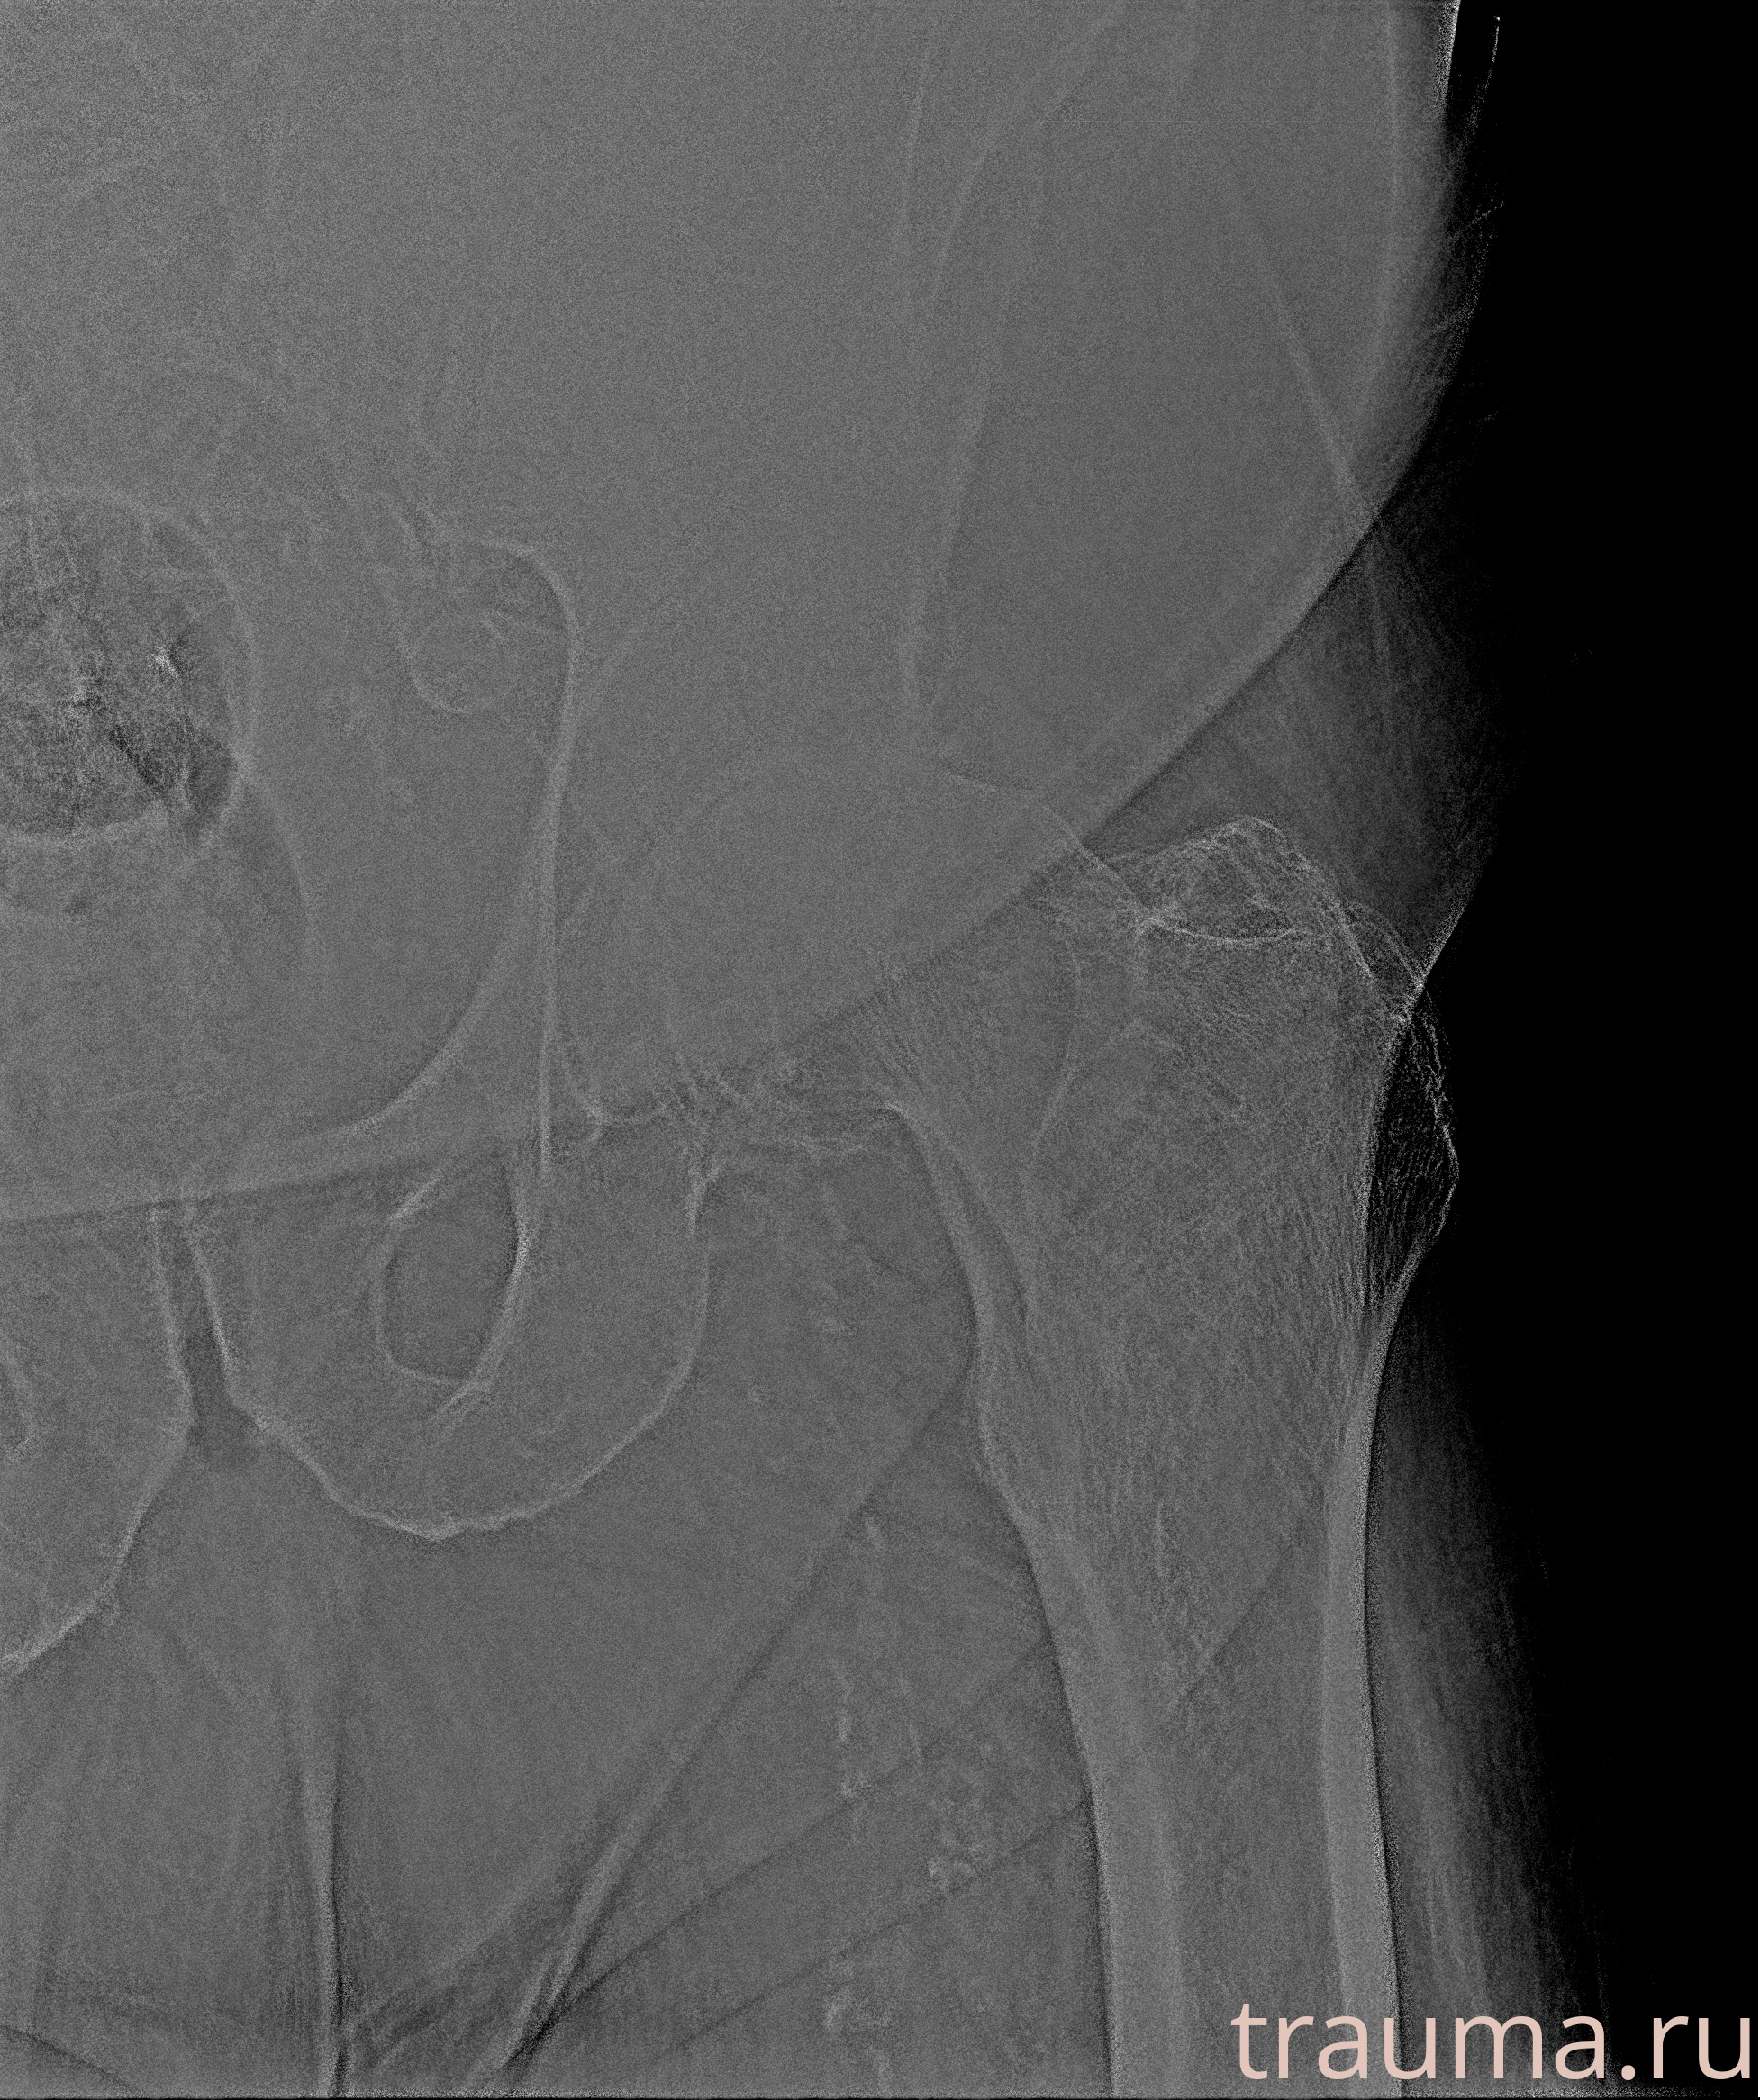

Рентгенограммы

Рентген на дому: по вашему адресу приезжает врач-рентгенолог, травматолог-ортопед с мобильным рентгеновским аппаратом, проводит диагностику травмы или заболевания, делает необходимые рентгенограммы, дает рекомендации по дальнейшему лечению. Получить качественные снимки в домашних условиях возможно благодаря уникальной методике, разработанной МосРентген Центром для института  Склифосовского